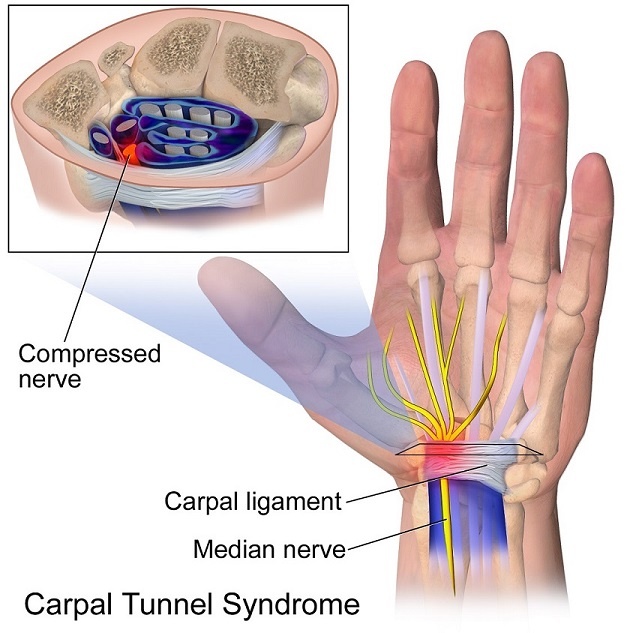

Do you know anyone with wrist or hand problems? Sometimes people will get pain from using the hands and other times it has nothing to